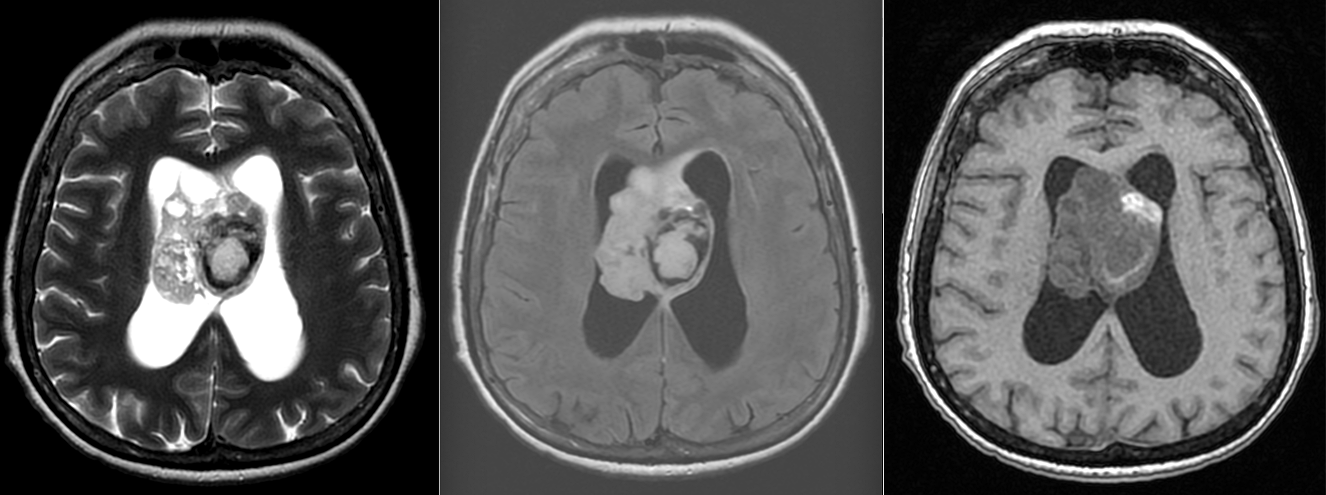

Imagistică – o tumoră „care se arată”

RMN-ul este, de cele mai multe ori, sugestiv:

- localizare intraventriculară, atașată de septul pellucid sau peretele ventricular

- aspect lobulat, uneori polilobat

- zone chistice și calcificări

- captare heterogenă de contrast

Pe CT, calcificările pot fi evidente și ajută la orientarea diagnosticului.